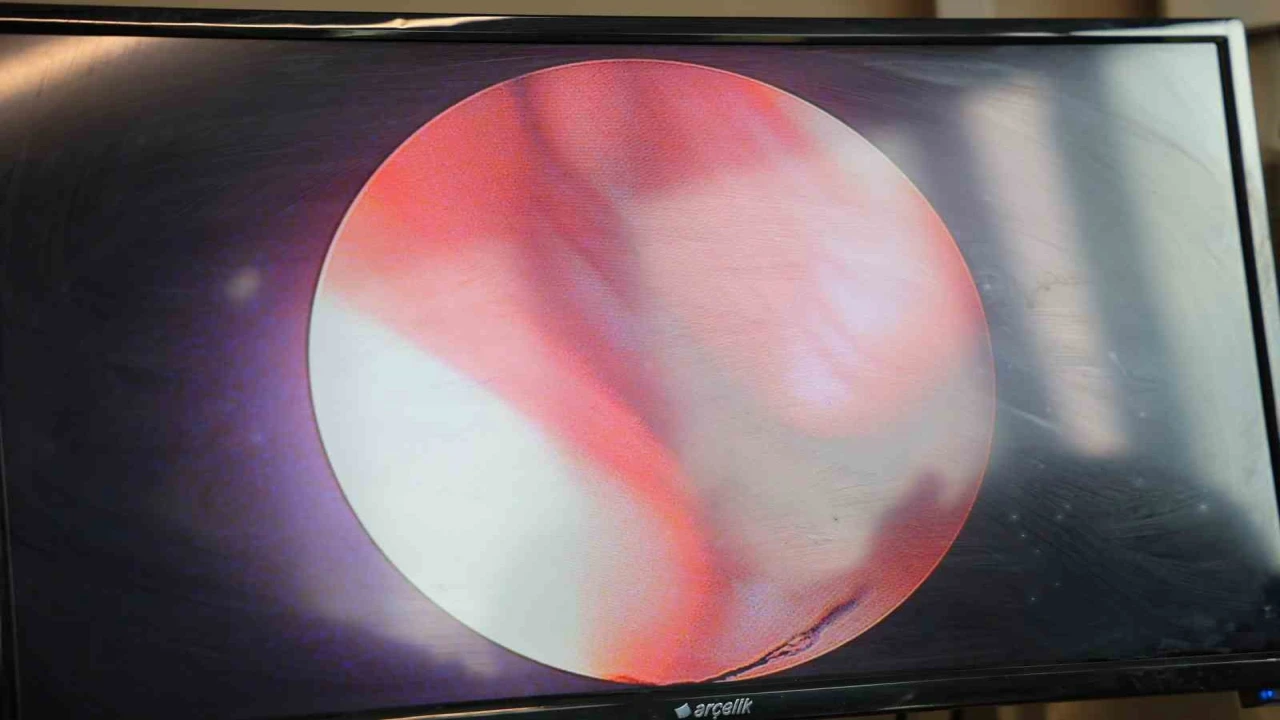

Kentin sanayileşmiş bir şehir olduğuna da değinen Okur, "Hava kalitesi etkilenebiliyor. Ve sanayide çalışan işçilerin orada kimyasala maruz kalması, toza maruz kalması artıyor. Bir başka durum da iki sene önce yaşadığımız elim vakadan sonra inşaat faaliyetlerinin artmış olması, çok fazla toz olması da alerji şikayetlerini arttırıyor. Çevremizde alerjiye sebep olan durumlardan kaçınmak gerekiyor. Evde özellikle nem ayarı, yüzde 50’nin üzerinde nemde halı akarı dediğimiz, halılarda yaşayan insan derileriyle beslenen canlıların miktarı artmış oluyor. Bunun dışında günlük sürekli kullandığımız yatak odamızda çarşaflarımızı 55 derecenin üzerinde sıcaklıklarla yıkayıp sık sık değiştirmek gerekiyor. Bunun dışında hamam böceğine karşı ve atıklarına karşı alerji olabiliyor. Bunu evimizden dışlamamız gerekiyor. Evinde hayvan besleyen hastalarımız oluyor. Bu hayvanlara karşı hassasiyeti olanlar olabiliyor. En azından yattığı odalarda hayvanlarla bir bölünmüşlük yaşarsalar daha iyi olabiliyor. Hastalığın tanısını koyma açısından cilt testi yapıyoruz. Cilt testi de alerjenleri hastaya az miktarda enjekte edip buna karşı derinin reaksiyonuna bakıyoruz. Bu hastanemizde yapılmaktadır. Bunun dışında alerjene özellik özel immunoglobinin dediğimiz kanda bir orana bakıyoruz. Bununla alakalı tanı koyabiliyoruz. Aslında esas tanımız hastanın şikayetlerinden yola çıkarak ve kliniğimizde muayene ederek tanı koyabiliyoruz" diyerek sözlerini tamamladı.